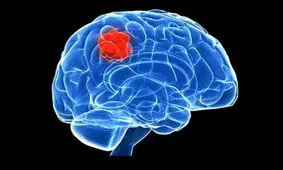

مطالعه جدید نشان میدهد سی تی اسکن که عمدتا در تصویربرداریهای پزشکی استفاده میشود ریسک تومورهای مغزی را افزایش میده…